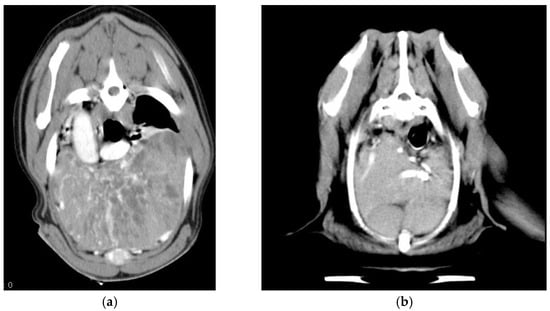

- Diagnostics: contrast-enhanced CT of the thorax without an angiogram was performed and available in 18 dogs; in older cases, medical records only reported three-view thoracic radiographs and thoracic ultrasounds for guidance in FNA of the mediastinal mass.